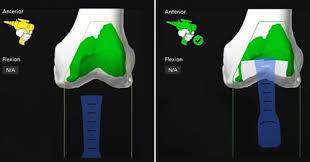

Introduction Knee pain can steadily reduce mobility and independence, especially …

Introduction to Robotic Knee Replacement Robotic knee replacement in Korba …

Introduction to Robotic Knee Replacement Robotic knee replacement in Khairagarh-Chhuikhadan-Gandai …